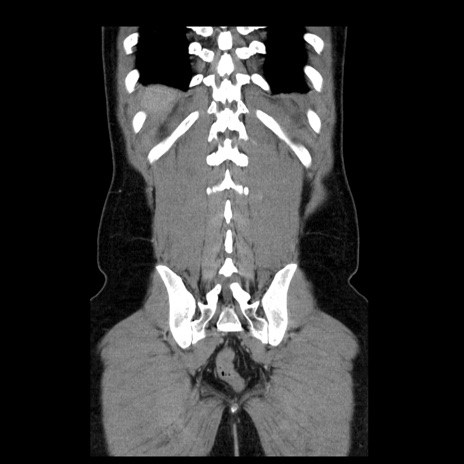

症例4(冠状断像)

【症例】30歳代男性

【主訴】腹痛、嘔吐

【現病歴】昨晩から突然の腹痛あり、その後嘔吐、軟便も出現。腹痛が改善しないため救急搬送となる。2日前にしめ鯖の食事歴あり。

【身体所見】意識清明、苦悶様、BP 135/90mmHg、BT 35.7℃、腹部:平坦、やや硬、心窩部〜臍部に自発痛、圧痛あり、筋性防御+、反跳痛-

【データ】WBC 8100、CRP 0.57